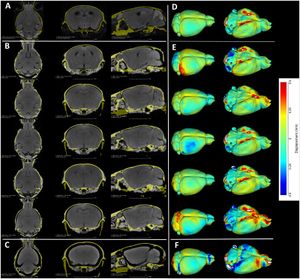

A. A representative high-resolution MRI scan of an age matched C57BL/6J displaying the brain and the mCT overlay (yellow outline) from [21]. B. Equivalent cross sections from five females that constitute the Group A (Hg perfusion) after 48h of staining in 2% I2KI. C. One individual that constitutes Group B (PFA perfusion) after 48h of staining in 2% I2KI. D-F: Heatmaps showing the difference in the obtained segmentations with respect to the reference MRI atlas constructed from [21,22]. To remove volumetric differences due to sex and age, we isometrically scaled our segmented brains to match the volume of the reference MRI atlas. Root mean square (RMS) errors are calculated after the scaling. D: Comparison of our Group A mCT atlas. RMS = 0.128 mm. E: Comparison of individuals of Group A. RMS values are 0.172 mm, 0.143 mm, 0.156 mm, 0.142 mm, 0.196 mm respectively. F: Comparison of Group B. RMS = 0.232 mm. All comparisons are rendered on MRI reference atlas. Grey area in the heat map indicate regions of large difference (>0.5 mm) either due to extreme shrinkage or difference in segmentation. Using this outline as the boundary, stained brains were interactively segmented using the editor module of 3D Slicer. |